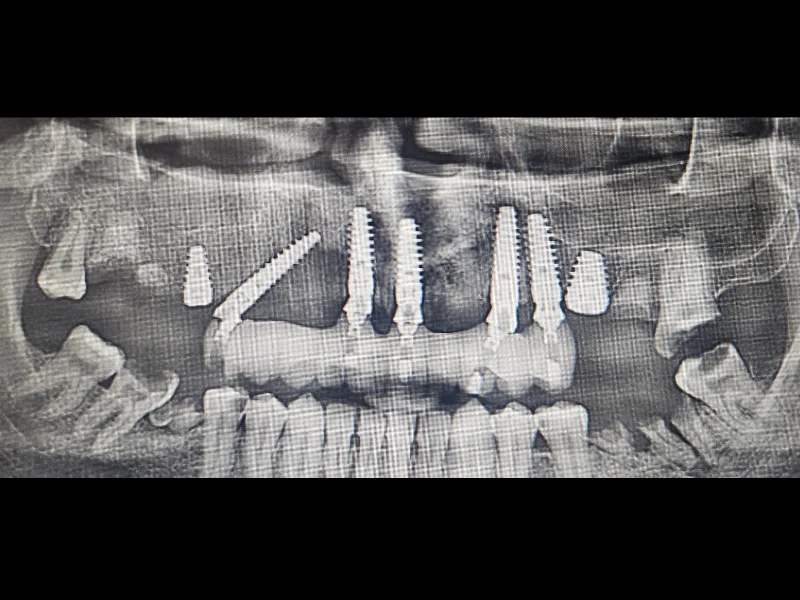

ALL ON 4/6 omogućava fiksne zube za nekoliko sati od ugradnje implantata. Zahvaljujući posebno planiranoj terapiji, savremenim implantatima i preciznoj tehnici ugradnje, implantati se mogu odmah opteretiti privremenim fiksnim radom koji pacijent ne skida. Implantati se postavljaju pod specifičnim uglovima kako bi se maksimalno iskoristila postojeća kost u prednjim regijama vilice i obezbedila stabilnost potrebna za nošenje fiksnog rada.

ALL ON 4 / ALL ON 6 koncept omogućava rešavanje i najzahtevnijih slučajeva nedostatka vilične kosti. Zahvaljujući naprednim tehnikama i specijalnim implantatima (zigomatični, pterigoidni i nazalni), moguće je pronaći stabilno i dugotrajno rešenje bez dodatnih komplikacija.